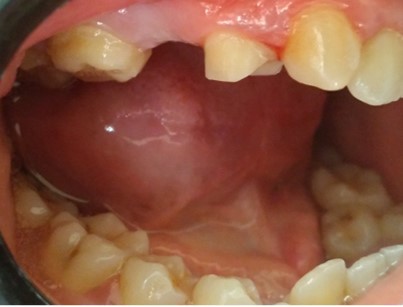

Before & After Gallery

Root canal treatment with crown restoration

Complex endodontic case